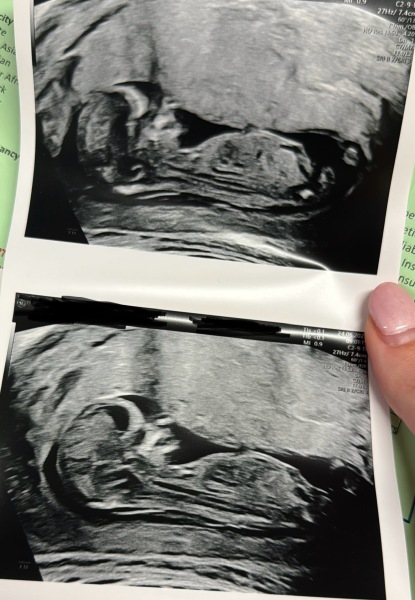

@Riverstardust @Nbaby i had my dating scan today 🥰 measuring at 13 weeks so caught up from the private scans! Waiting for the screening results but NT measurement and everything else looked good! They were upside down for the entire scan despite best efforts 🤣

Any gender guesses from the nub theory?? 🤭